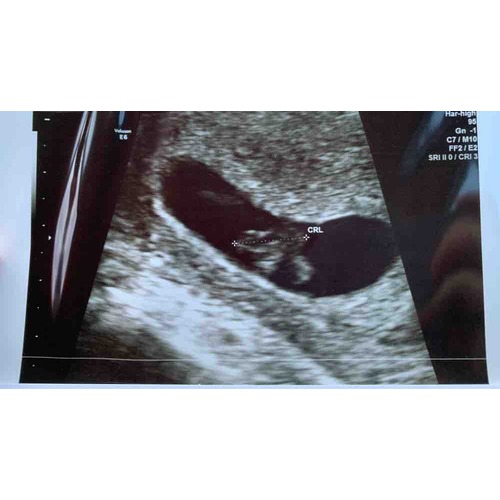

Hoi allen, hoe is het uiteindelijk bij jullie allemaal verlopen? Wij hadden gister onze eerste echo (ongeveer 6.3 wk) en onze Vk was ook wat voorzichtig met goed nieuws brengen door de vorm van de vruchtzak. Echter wel een hartslag; langzaam maar dit hoeft nog niets te betekenen met dit termijn.

Ik heb tijdens bloedverlies twee echo's gehad met een kloppend hartje. Veel stolsels ook om de vruchtzak heen in mijn baarmoeder.